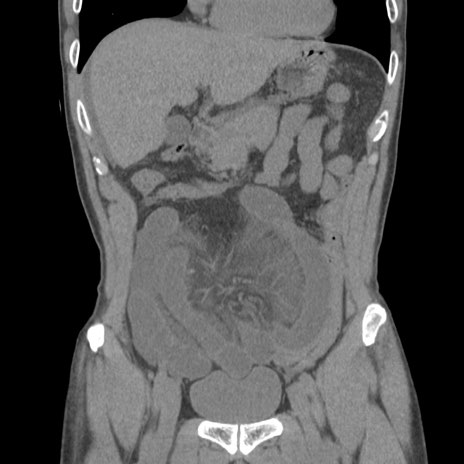

症例56 CT(冠状断像)

横断像